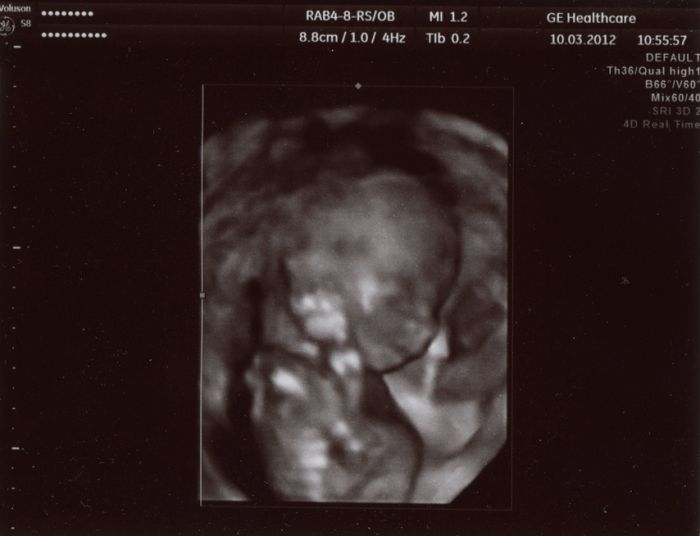

Tady je pár foteček. Video dostanu za 2 týdny až tam půjdu na kontrolu. Ten jeho přístroj mu to nedovede hned zpracovat, tak nám to video nemohl hned dát.